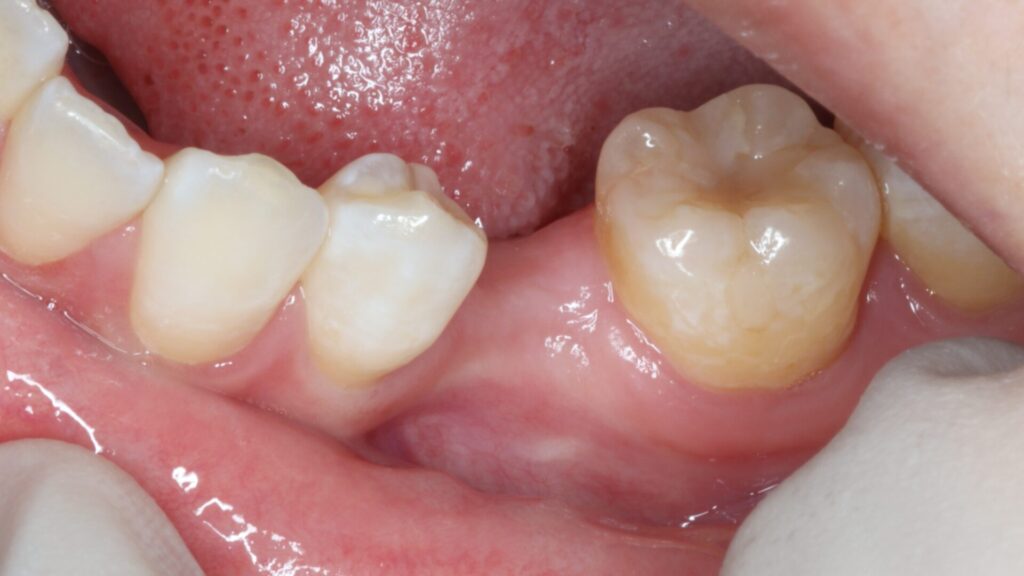

左下に永久歯が先天的にない部分へのインプラント治療を希望されて来院された患者様

左下に永久歯が生まれつき1本少なく乳歯が残っていたところが抜歯となり、インプラント治療を希望されて遠方から当院に紹介来院されました。

永久歯の先天欠如は珍しいことではなく、特に第二小臼歯(前から5番目の歯)に多くみられます。前後の歯も含めて虫歯もなく、このような状態を回復させるのにはインプラントが最適です。